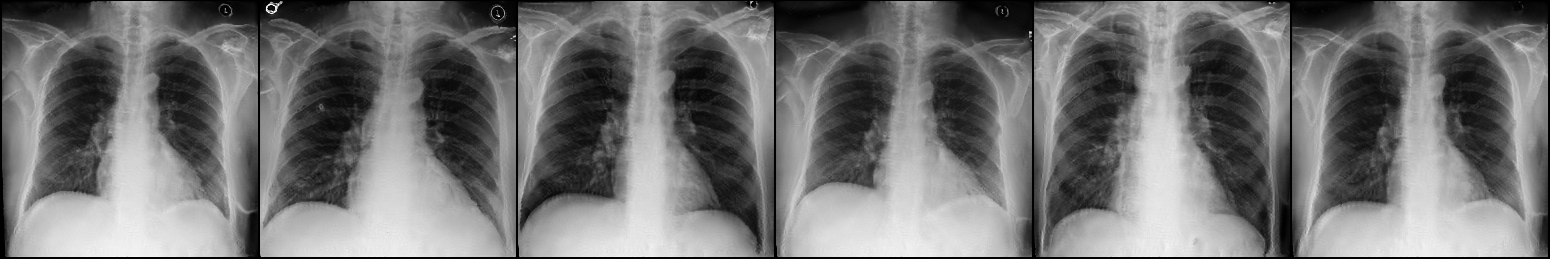

Fig. 3: Anonymization results. Real images XRX_{R} randomly selected from the training, validation, and test sets are displayed in the first column. The corresponding reconstructed images X^R\hat{X}_{R} are displayed in the second column. The anonymized images XAX_{A} are displayed in the last three columns.

Qualitative Results The visualization results are shown in Fig. 3. In this figure, the anonymized images optimized using only the utility loss ut\mathcal{L}_{ut} (column 3) exhibit greater visual similarity to their real counterparts (column 1), while those optimized using only the identity loss id\mathcal{L}_{id} (column 4) appear more distinct from their originals. Additionally, the anonymized images optimized with both the ut\mathcal{L}_{ut} and the id\mathcal{L}_{id} (column 5) strike a balance, appearing more realistic by simultaneously considering both identity removal and utility preservation.